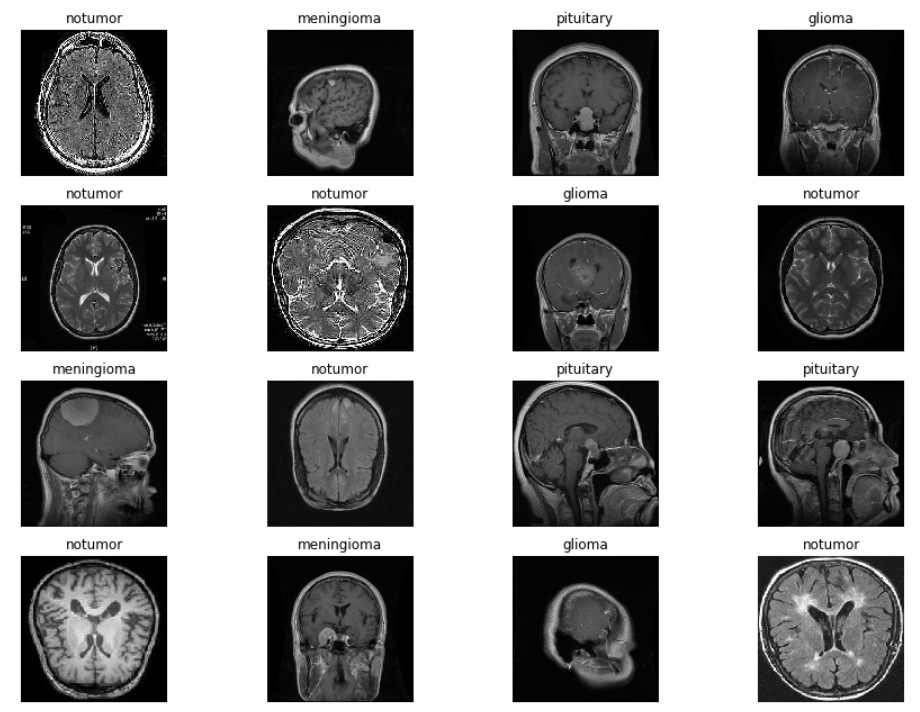

现在让我们通过可视化我们的图像来观察图像增强是如何工作的,并通过使用我们的分类器来识别我们正在寻找的脑肿瘤类型。

现在我们将通过调用我们定义的函数来绘制我们的图像。

#Call the plotImages function

plotImages(x,y)

它会给我们这样的输出,

现在,该项目最重要的一步是开始使用卷积神经网络创建深度学习模型。